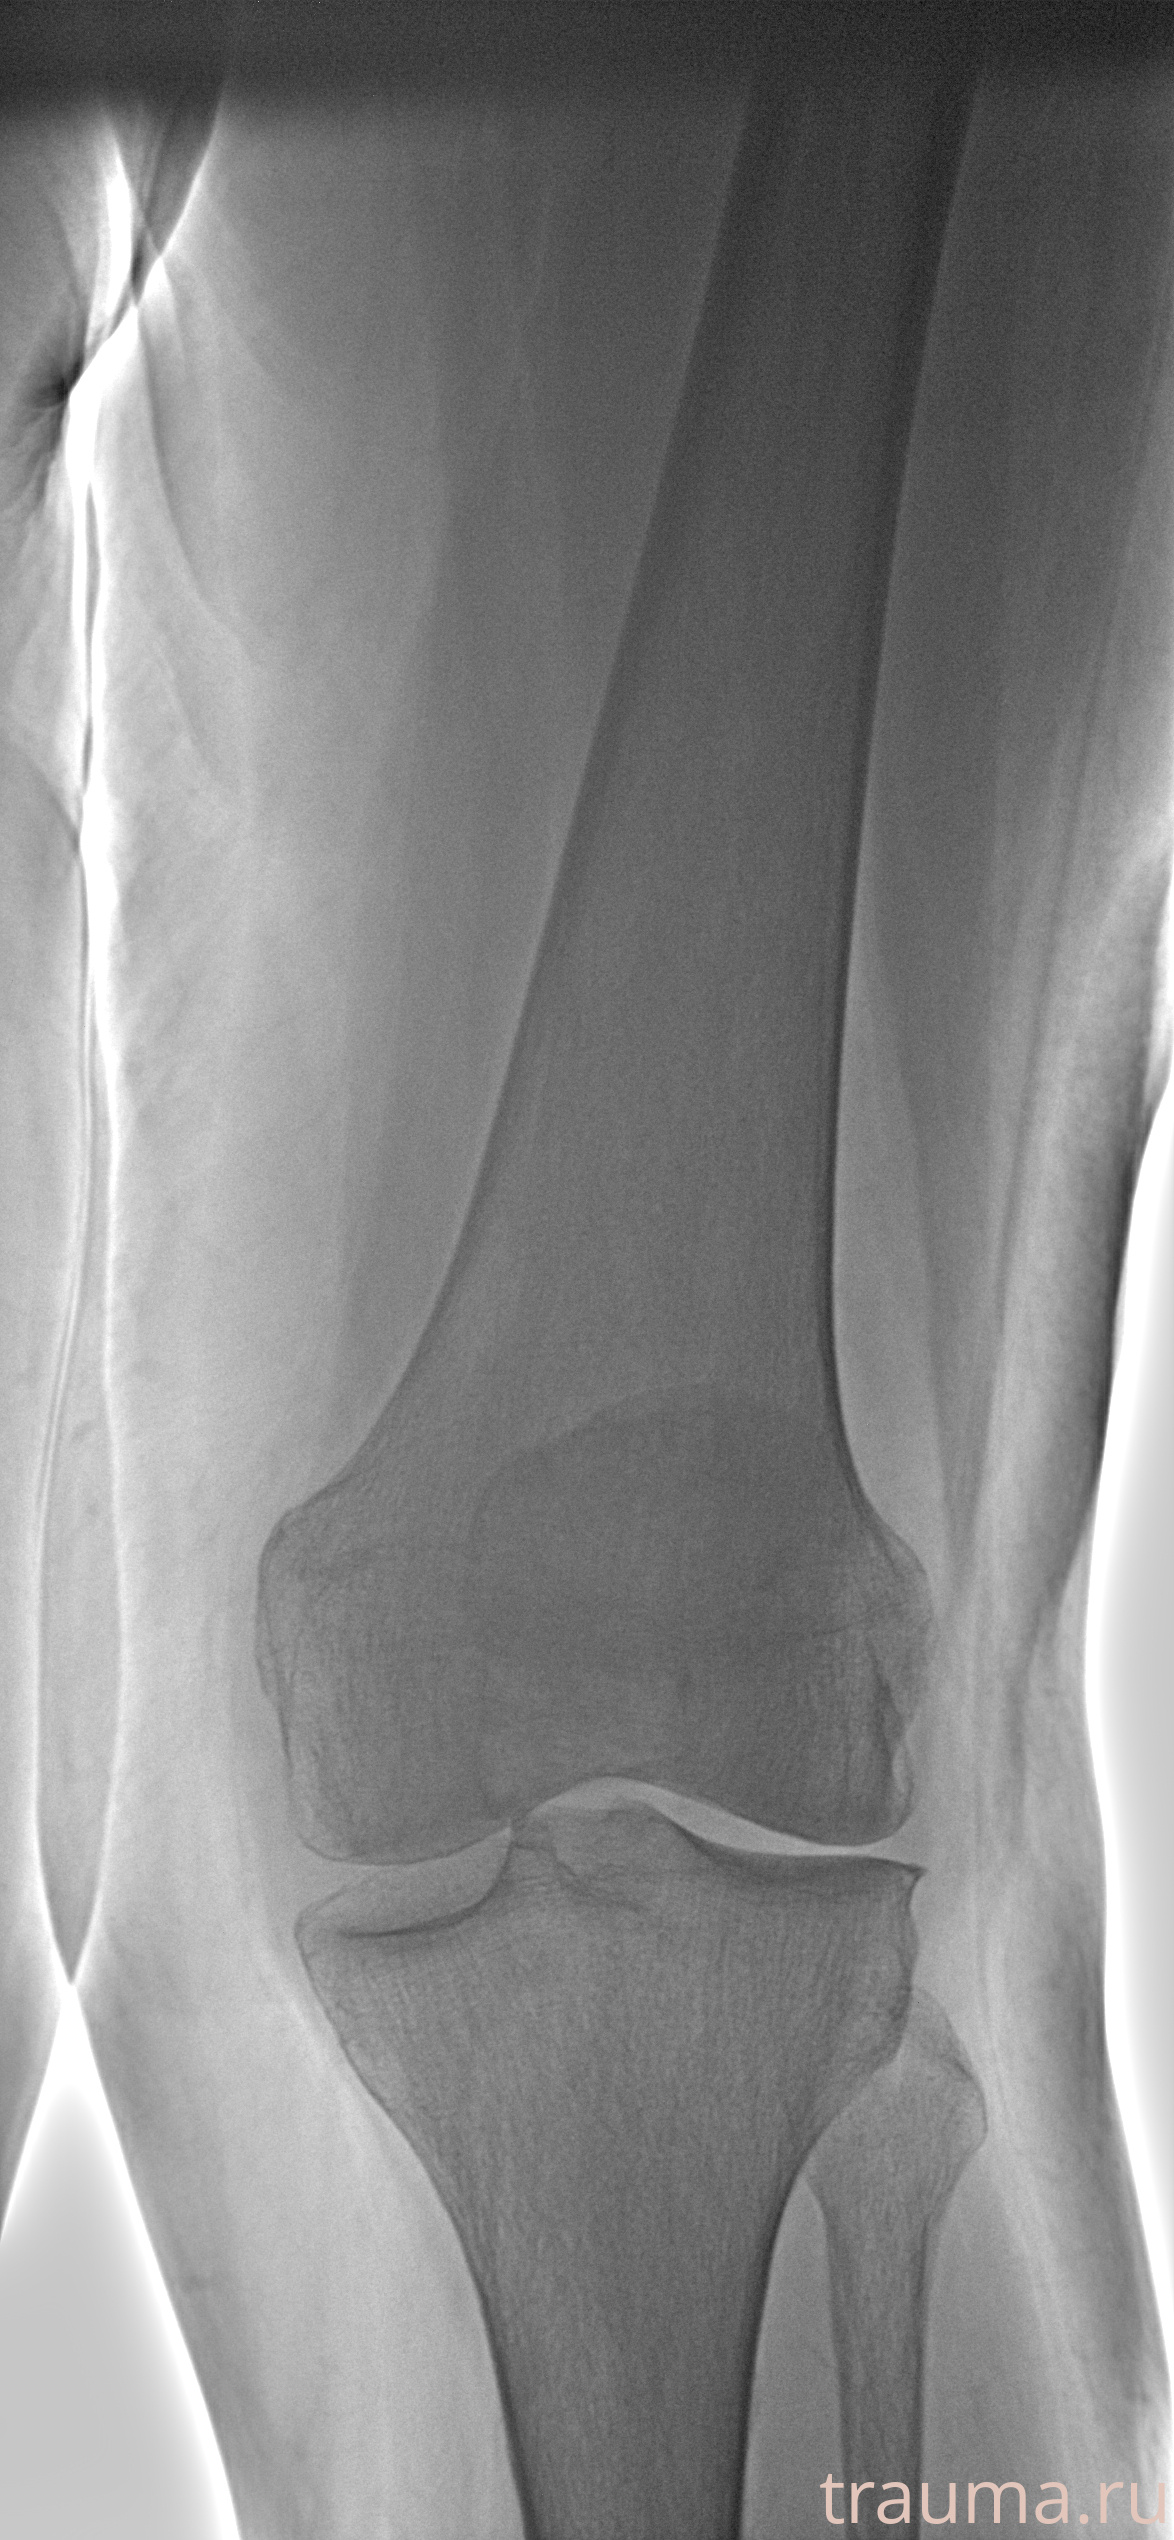

Рентген на дому: по вашему адресу приезжает врач-рентгенолог, травматолог-ортопед с мобильным рентгеновским аппаратом, проводит диагностику травмы или заболевания, делает необходимые рентгенограммы, дает рекомендации по дальнейшему лечению. Получить качественные снимки в домашних условиях возможно благодаря уникальной методике, разработанной МосРентген Центром для института  Склифосовского

при переломе шейки бедра и пневмонии от компании МосРентген Центр - партнера Института имени Склифосовского